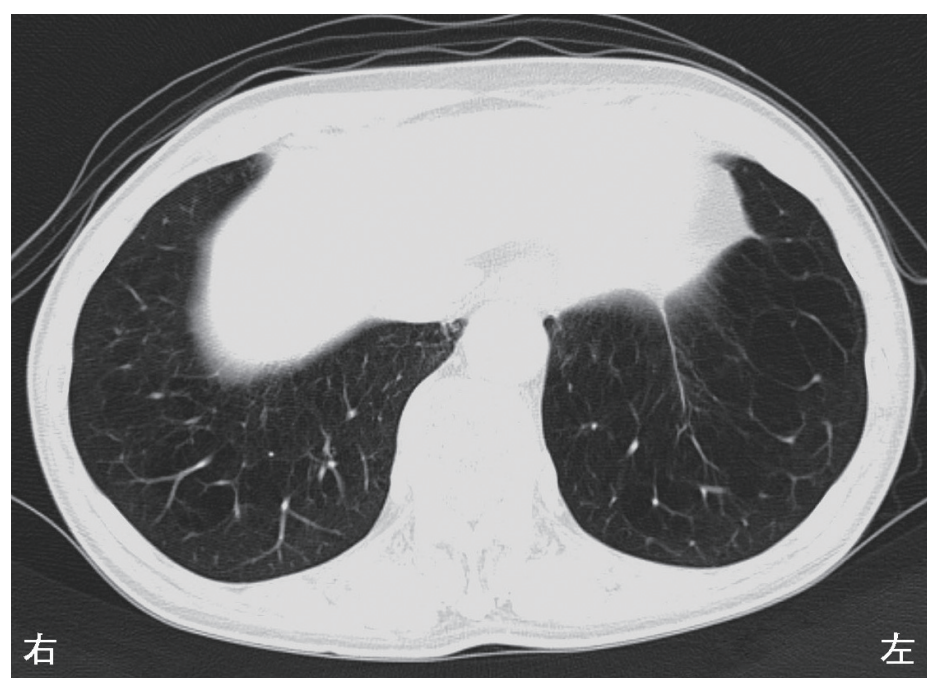

80歳の男性。胸部CTを別に示す。

この患者で低下が予想されるのはどれか。